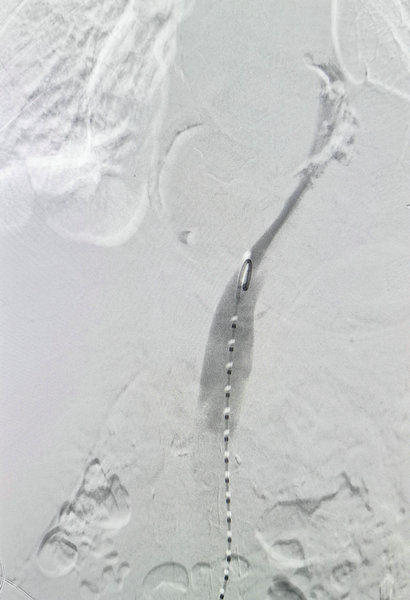

术中造影显示破口较大真腔受压明显

造影显示主动脉夹层形成